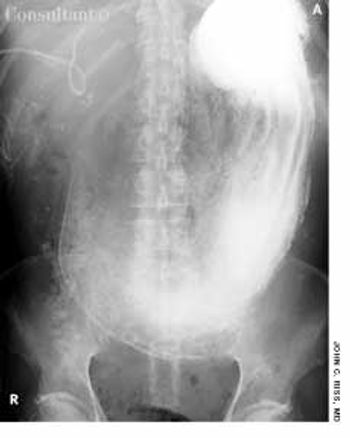

A 17-year-old girl presented to the emergency department with abdominal pain, nausea and vomiting, and diarrhea approximately 9 hours after swallowing 25 tablets (200 mg each) of iron sulfate in a suicide attempt. Her vital signs were within normal limits. She was mildly lethargic; stool was hemoccult-positive.